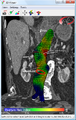

An aneurysm ruptures if the mechanical stress (tension per area) exceeds the local wall strength; consequently, peak wall stress (PWS),[30] mean wall stress (MWS),[31] and peak wall rupture risk (PWRR)[32] have been found to be more reliable parameters than diameter to assess AAA rupture risk. Medical software allows computing these rupture risk indices from standard clinical CT data and provides a patient-specific AAA rupture risk diagnosis.[33][34][35] This type of biomechanical approach has been shown to accurately predict the location of AAA rupture.[34][35][36]

Biomechanical AAA rupture risk prediction